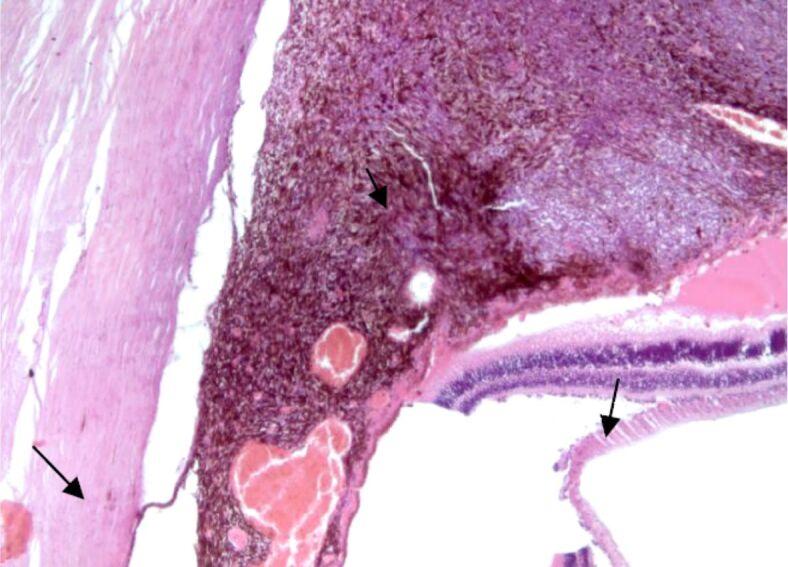

Ocular melanoma is a rare but complex disease in current medical practice. Our retrospective study spans over a period of 28 years and analyzed uveal and conjunctival melanomas that were consecutively admitted, diagnosed, and treated in the 2nd Ophthalmology Clinic of Prof. Dr. Nicolae Oblu Emergency Clinical Hospital, Iaşi, Romania. The patients were selected from the records of the Department of Pathology of our Hospital, being diagnosed by standard histopathological techniques. The aim of this study was to summarize the epidemiological and pathological aspects of uveal and conjunctival melanomas in Northeastern region of Romania. In our study, we did not notice a predilection of uveal and conjunctival melanoma to one particular gender. The most common histological subtypes of ocular melanomas were the heavily pigmented spindle cell subtype, followed by the epithelioid subtype. Our patients sought medical help in a timely manner, before the systemic invasion of the disease could develop.

在当前的医学实践中,眼黑色素瘤是一种罕见但复杂的疾病。我们的回顾性研究跨越了 28 年的时间,分析了在罗马尼亚雅西的尼古拉·奥布卢教授急诊临床医院第 2 眼科诊所连续收治、诊断和治疗的葡萄膜和结膜黑色素瘤。这些患者是从我们医院病理科的记录中选择的,通过标准的组织病理学技术进行诊断。本研究的目的是总结罗马尼亚东北部葡萄膜和结膜黑色素瘤的流行病学和病理学特征。在我们的研究中,我们没有注意到葡萄膜和结膜黑色素瘤对某一特定性别的偏好。眼部黑色素瘤最常见的组织学亚型是高度色素化的梭形细胞亚型,其次是上皮样亚型。我们的患者在疾病发生全身侵袭之前及时寻求了医疗帮助。